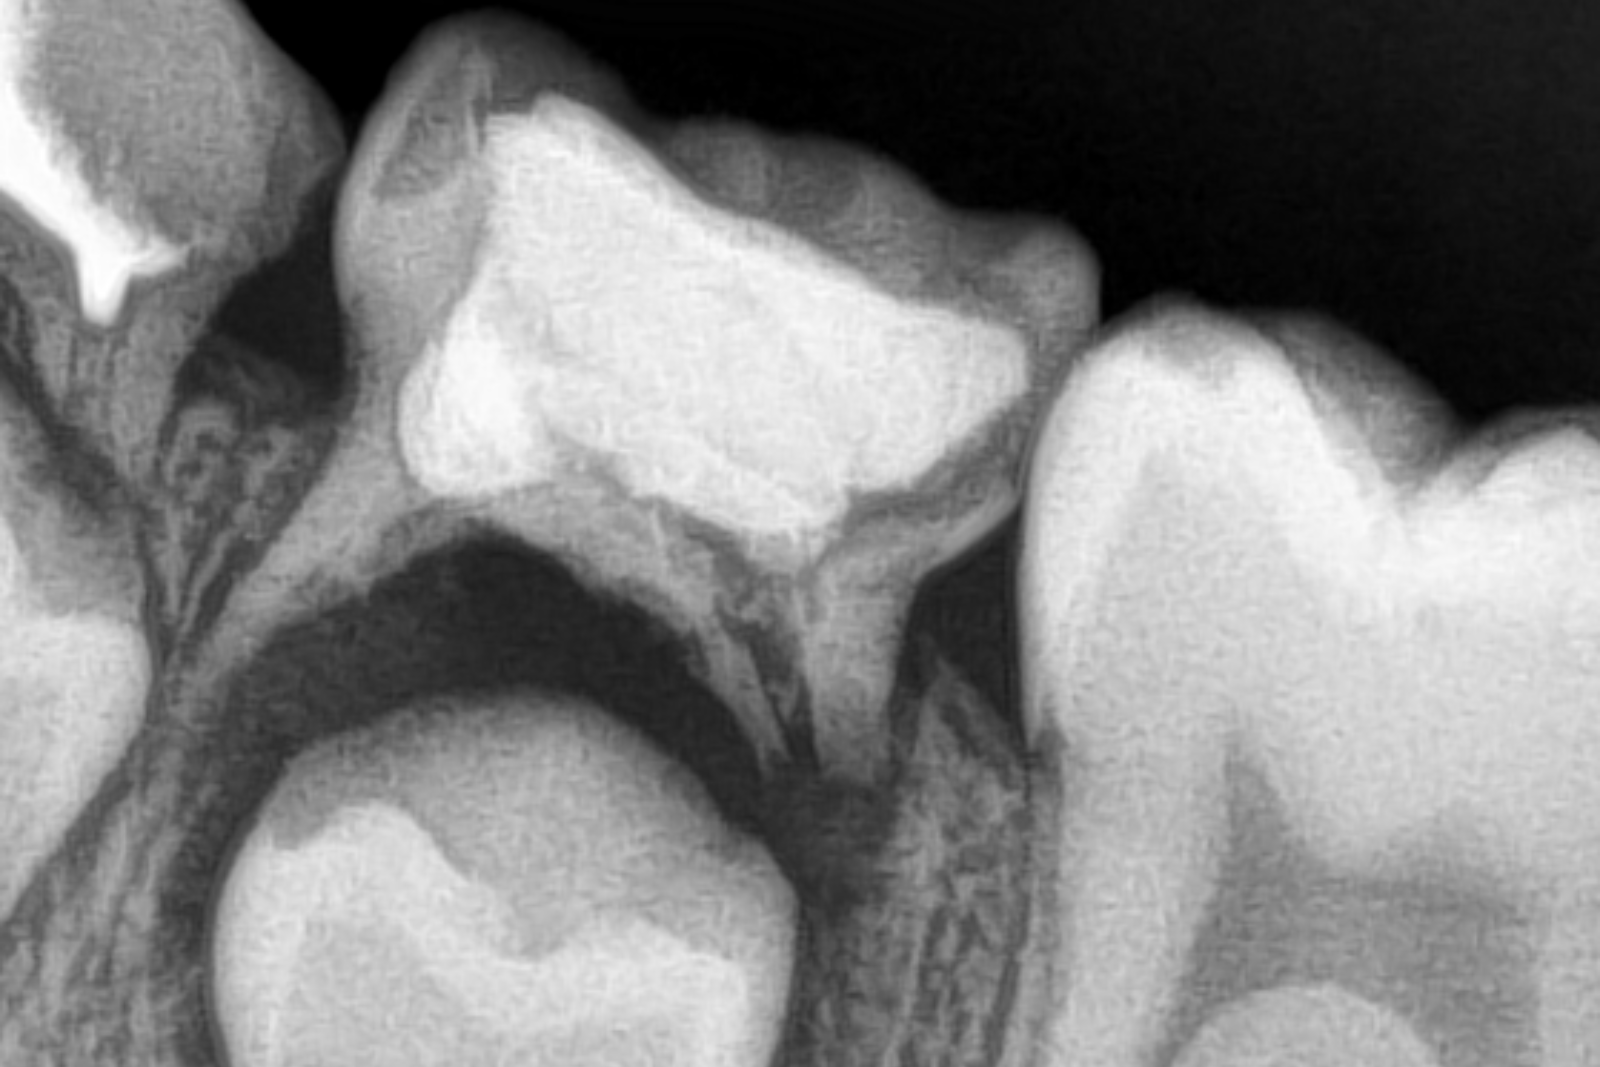

После того как анестезия подействует, врач начинает удаление зуба с использованием специализированных инструментов. В некоторых случаях процедура может проходить под контролем рентгеновского аппарата, что позволяет обеспечить максимальную точность и безопасность.

Удаление молочного зуба